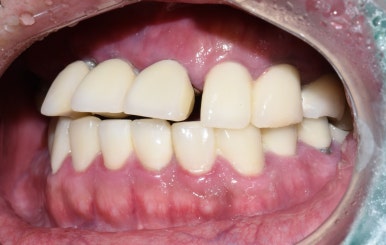

앞니 브릿지가 많이 흔들려요. 어금니도 없어요

치료 전

앞니 브릿지가 많이 흔들려요. 어금니도 없어요 라고 말씀하시며 온 환자분입니다.

앞니 뿌리 주변에 뼈가 뿌리를 지탱해주지 못해서 앞니는 흔들리는 상태여서

발치 후 임플란트를 진행하였습니다.

임플란트로 치료 후 사진 (윗니는 모두 전체임플란트)